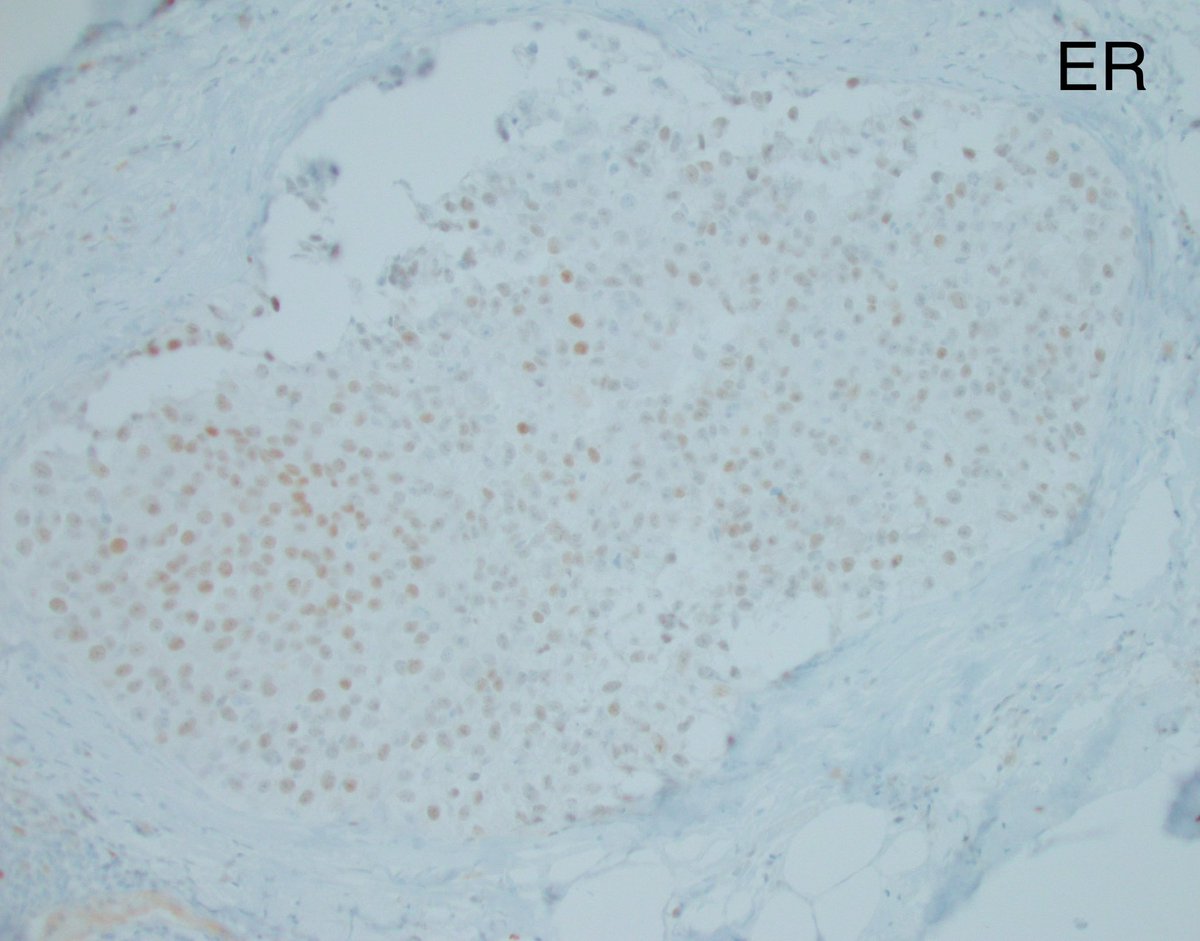

As a follow up to yesterday’s post, CK5/6 and ER are not very useful and can be confusing when the intraductal proliferation consists of a pure population of intermediate and high grade nuclei. DCIS can show basal-like immunophenotype (CK5/6 positive) and can be ER variable to